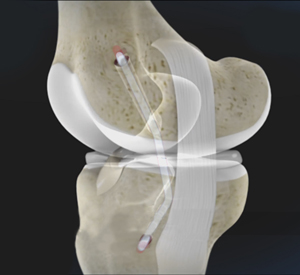

PCL Reconstruction

PCL Reconstruction Specialist in Palm Beach Gardens & Wellington The PCL is usually injured by a direct impact during an automobile accident …